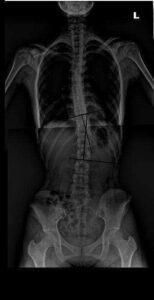

측만증(scoliosis)이란 척추가 뒤에서 봤을 때 반듯하게 서 있어야 하는데 C자 모양, S자모양, 역 S자 모양 등으로 변형되는 걸 말하며 심하면 척추 자체가 회전되어 변형되기도 합니다. 또한 더욱 중요한 것은 옆에서 본 모습에서도 정상적인 척추 만곡이 S자 모양을 이루어야 하는데 대개는 허리 부분의 만곡이 더욱 커져서 허리가 앞으로 밀려가고 배가 볼록 나오게 되는 과전만 형태를 겸하게 됩니다.

측만증은 원인에 따라 크게 비구조적 척추측만증과 구조적 척추측만증으로 나눌 수 있지만 갑작스러운 근육통 등으로 허리가 틀어지는 기능적 측만은 통증이 사라지면 소실되는 측만증이므로 측만증 자체가 문제가 되지 않지만 문제가 되는 측만증은 우리 아이들에게 원인이 밝혀지지 않고 생겨나는 측만증입니다. 이 특발성 척추측만증은 80%을 차지하며 진행성인 경우가 많아 적절한 치료를 하지 않을 경우 증상이 계속 심해질 수 있으며 통증과 기형을 유발합니다. 대개는 역 S자 모양이 많아서 우측 등, 좌측 허리가 볼록하게 튀어나옵니다.